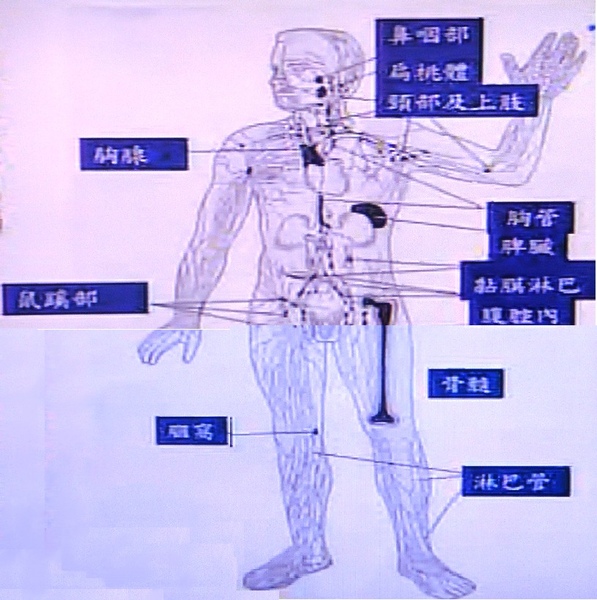

淋巴癌 @ Sunday 商天 :: 痞客邦

淋巴引流综合消肿疗法(CDT)技术 – 知乎

淋巴堵塞,身體會出現2腫、1癌,2招分分鐘疏通淋巴 – 每日頭條